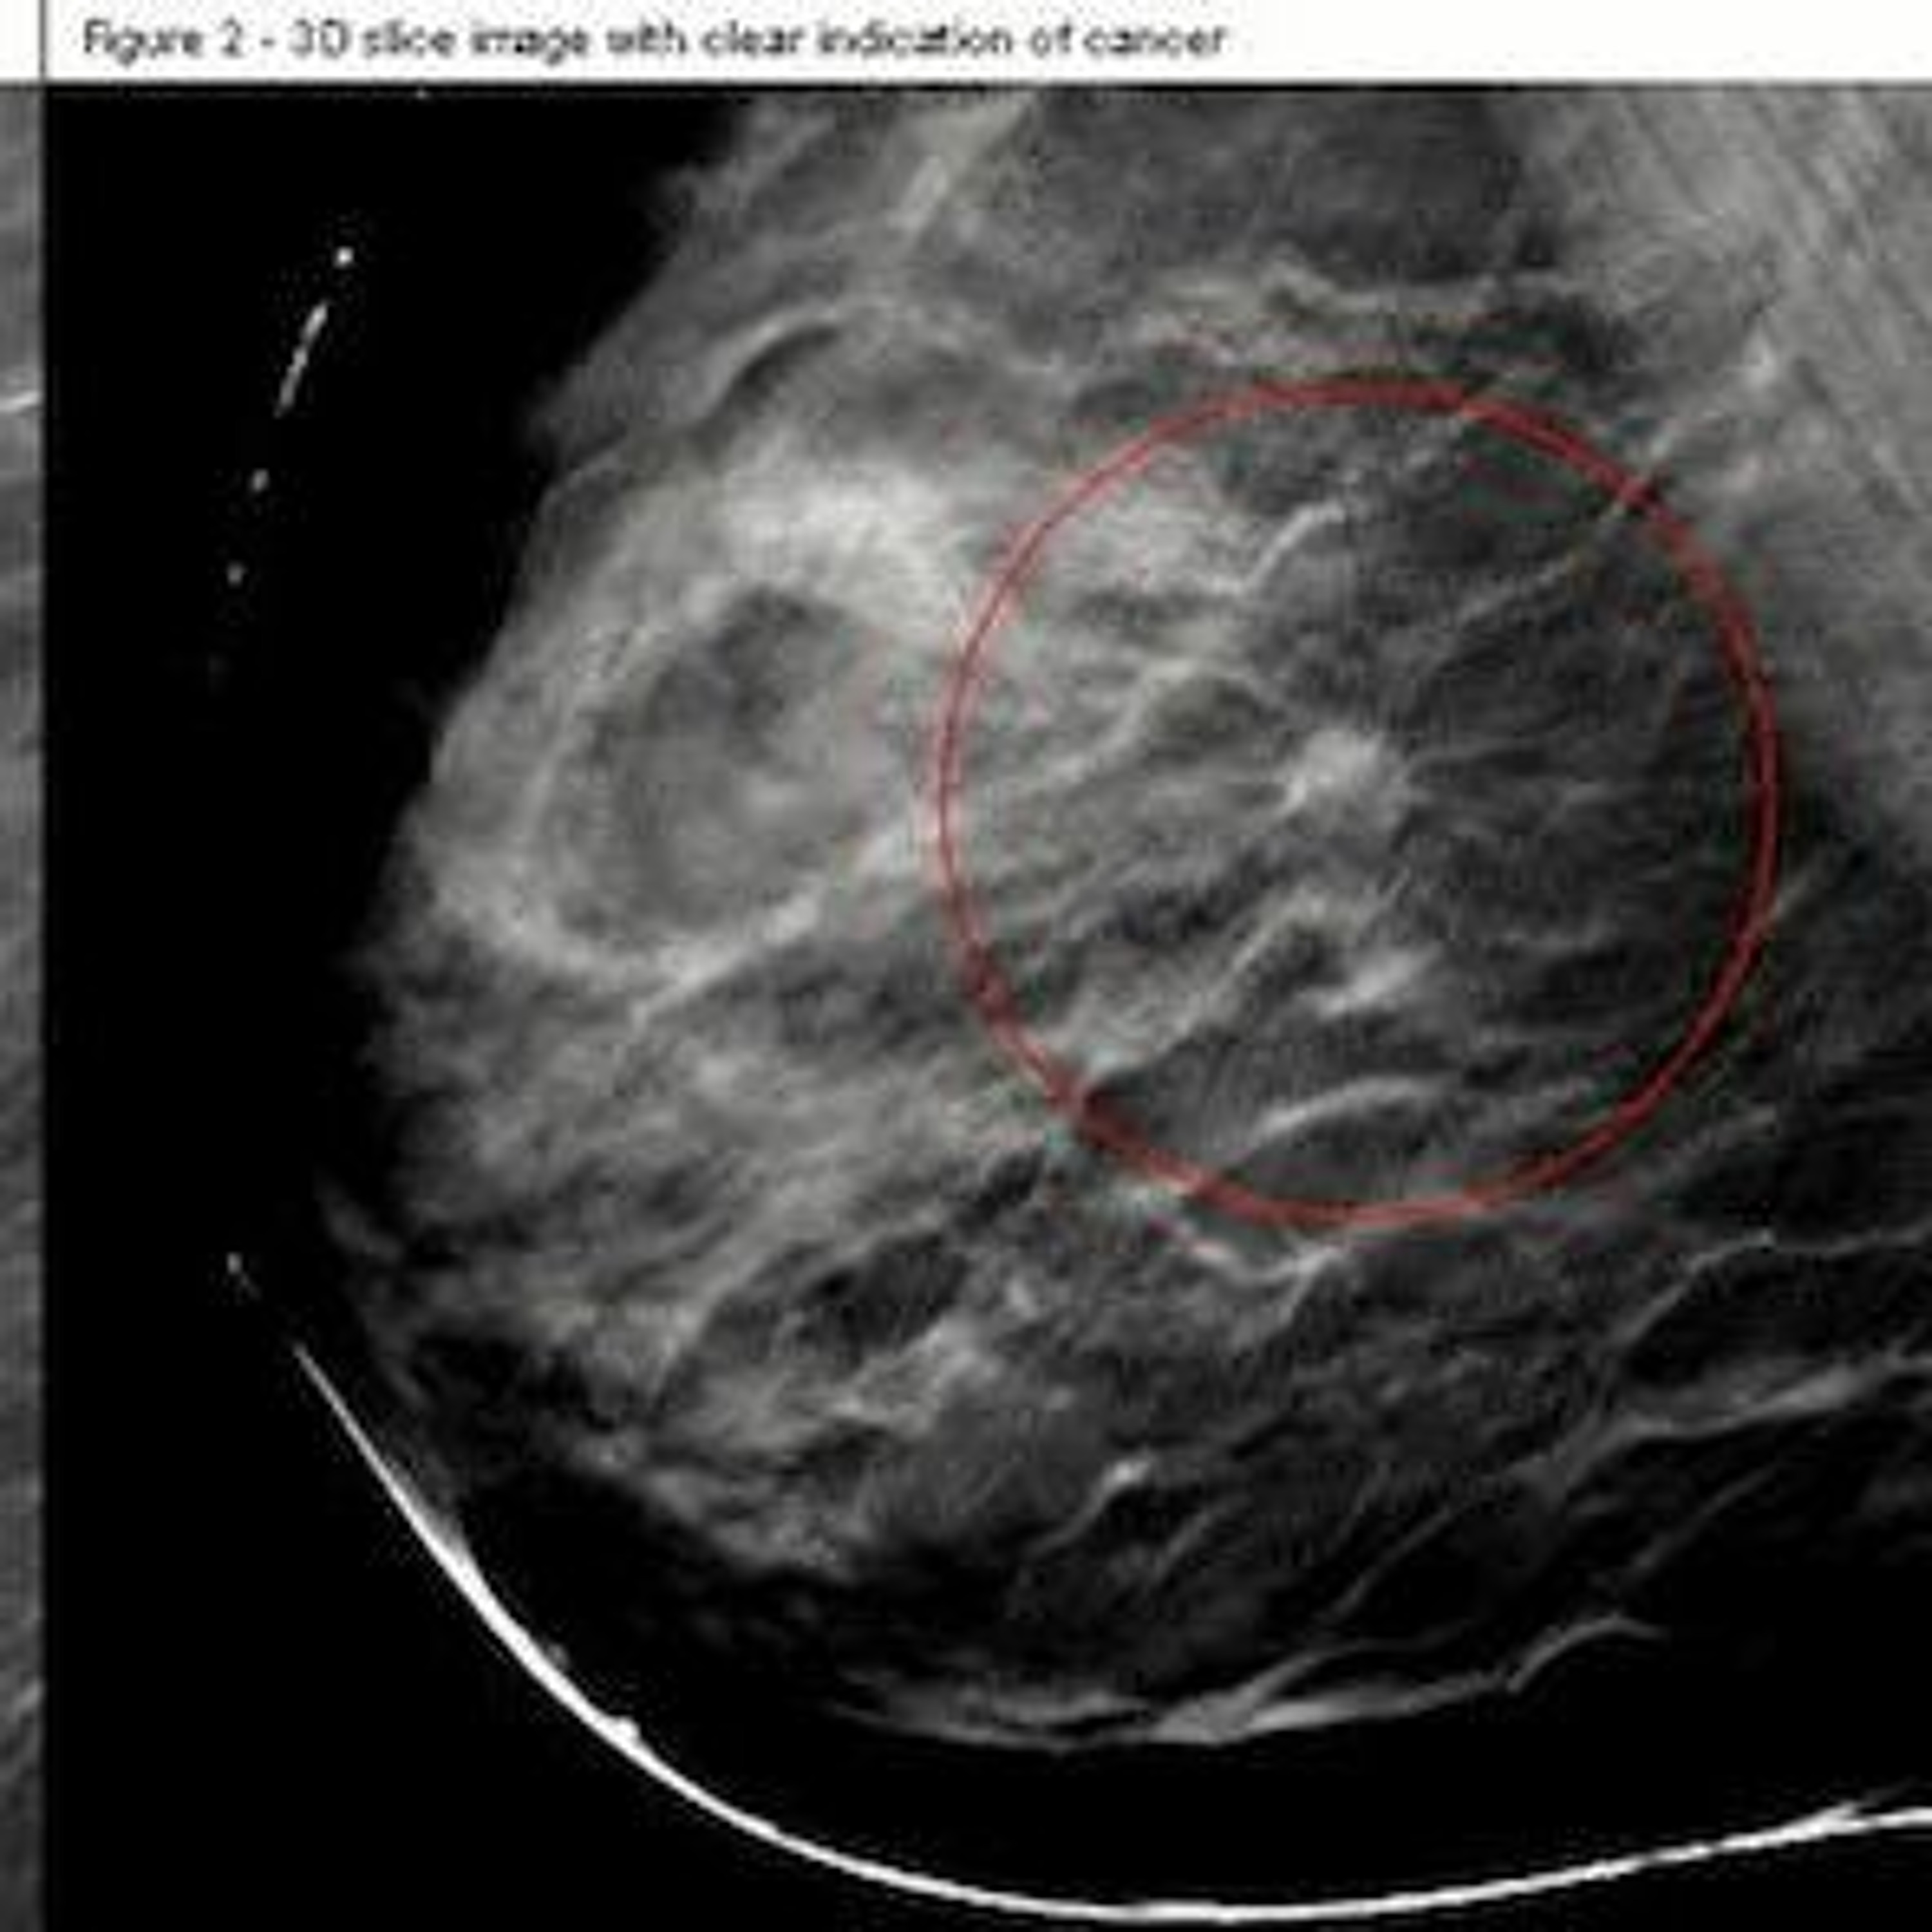

A 3D mammogram could be more effective for women with dense breasts than a regular mammography test. That’s because a three-dimensional scan is easier to detect abnormalities in dense tissue. This according to breast cancer researcher Karla Kerlikowske of University of California, San Francisco.